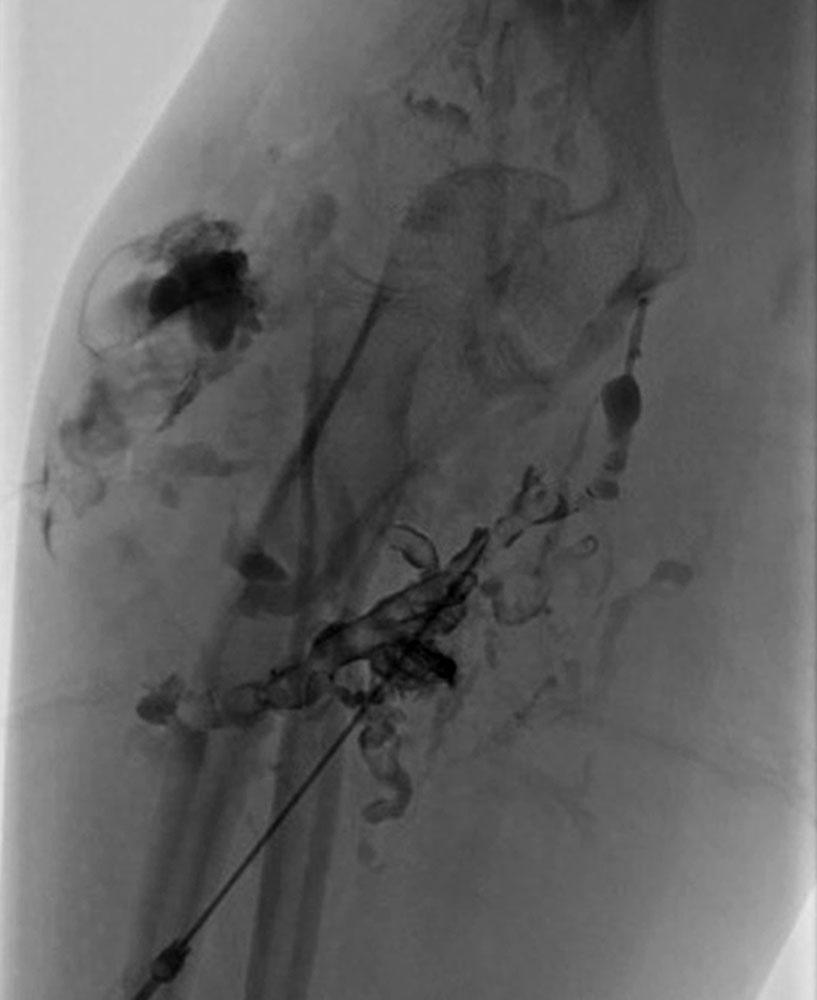

Thrombophlebitis is also depicted in direct phlebography or varicography (in the context of therapy). Intravascular thrombi present themselves as local non-contrasted areas within a vessel. Thrombophlebitis per se is not an indication for phlebography.

It is important to know whether patients with larger venous malformations have venous communications draining to the deep conducting venous system. If these connections are present and have a large lumen, clinically relevant blood clots may drain off from the venous malformation and cause thromboembolism with thrombosis and / or pulmonary embolism. Detection of these connections (from VM to deep venous system) is best accomplished with direct phlebography. If detected, these communicating veins should be occluded.